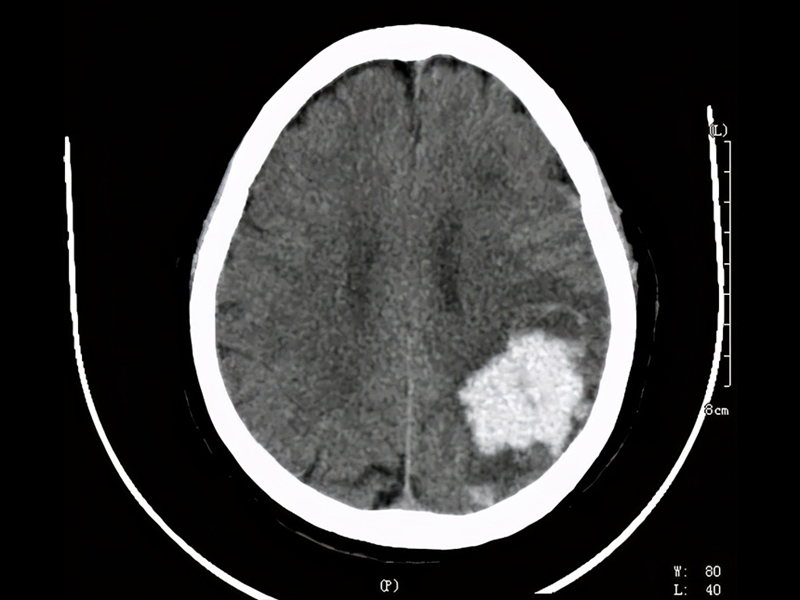

瀏覽:1158 7 點起床 1 點睡覺,腦幹出血 ICU 抢救 | 瀏覽:3169 14 種可緩解便秘的食物 | 瀏覽:1606 港鐵列車緊急停駛,少年打開逃生門引混亂 |